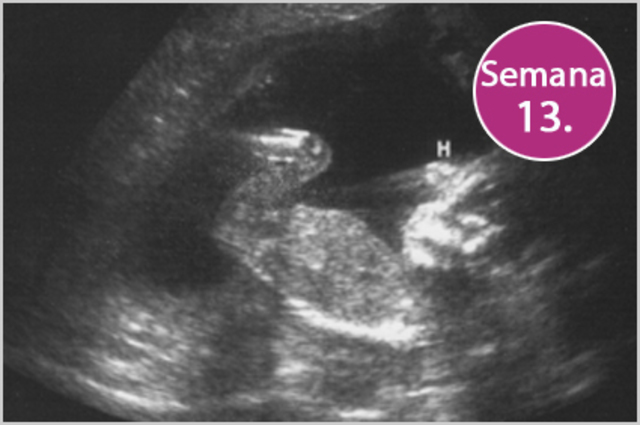

• Semana 13

Semana 13

-El feto capta sonidos.

-El crecimiento del feto es mucho más rápido.

-La osificación del esqueleto fetal es activa.

-Los huesos son claramente visibles en imágenes ecográficas.